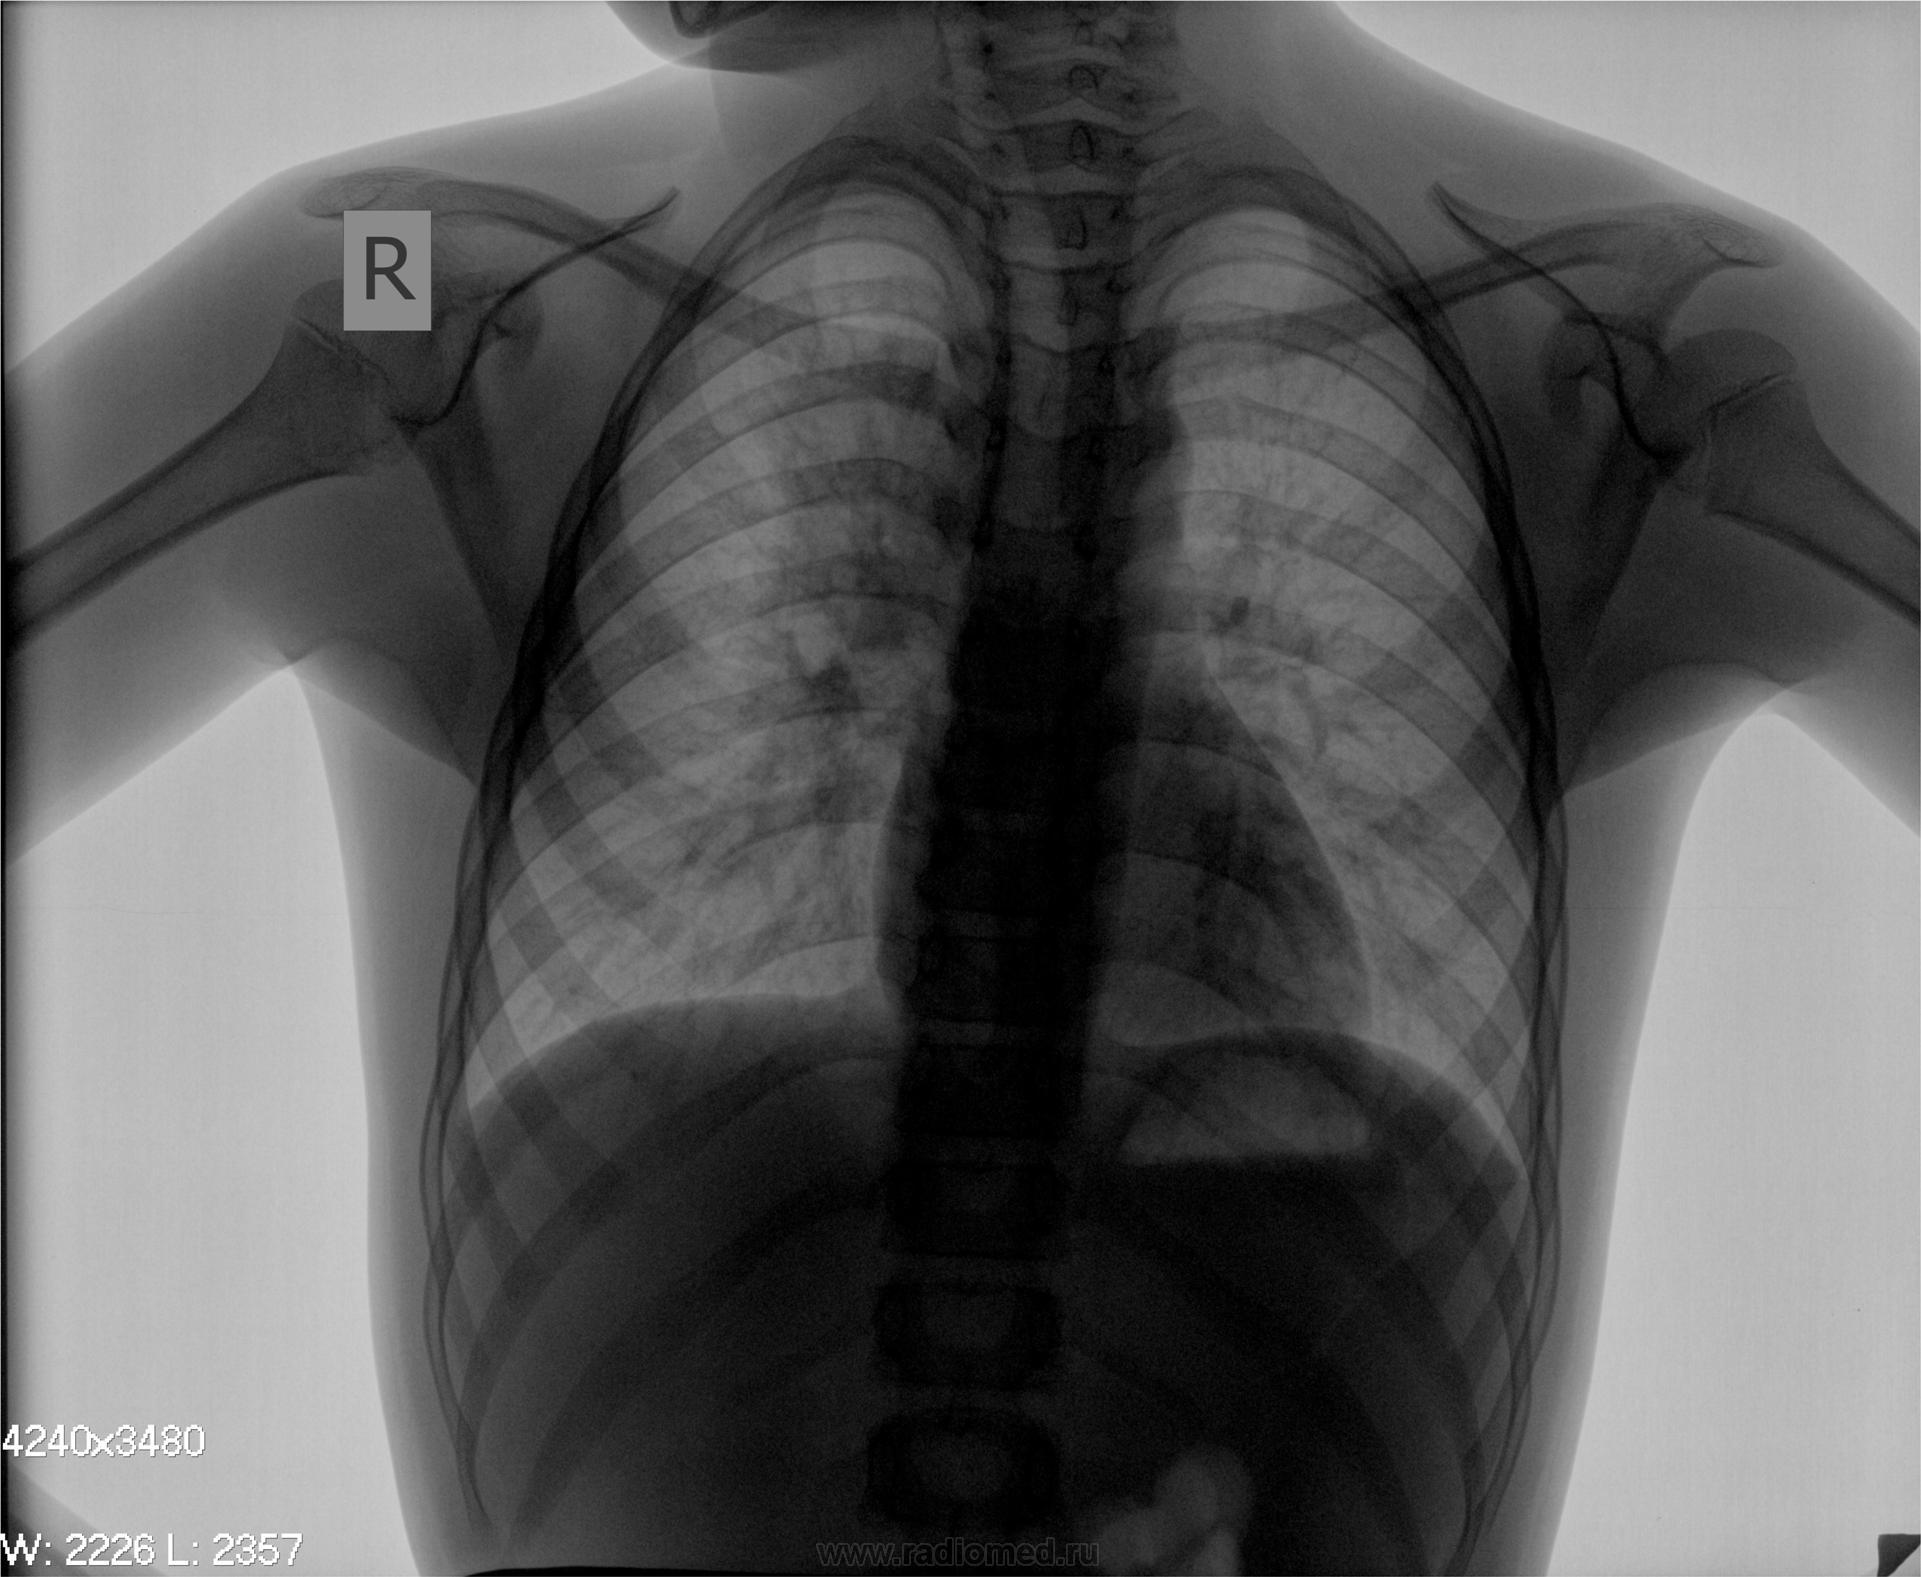

Мальчик 2000 г.р., направлен педиатром с диагнозом: Пневмония?

снимки

ogk.jpgogk_2.jpg

надо делать боковые снимки. Пора кончать эту многолетнюю порочную практику в педиатрии. На сайте Радиомед обсуждался вопрос о врачах, которые не назначают боковые снимки. Все были единодушны. С уважением Nik

Да, боковой очень желателен. Может, инфильтрация в 6-ке или 3-ке, а может в прикорневой зоне. В любом случае, сначала антибактериальная терапия с последующим рентгенконтролем, а там видно будет.